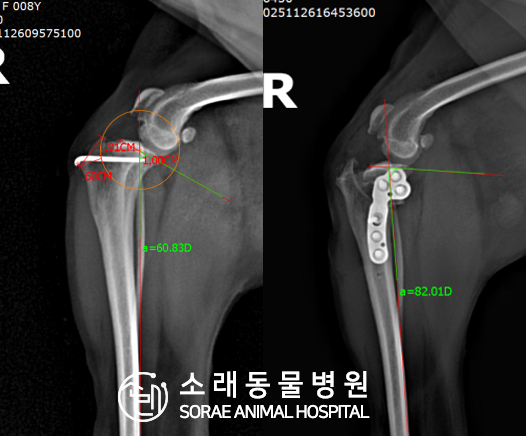

계산식으로 사전에 계획해두었던 플랜에 따라 경골을 절제하고

플레이트와 스크류를 사용하여 임플란트를 적용해 주었습니다.

반대 방향으로 밀려나 어긋나있던 대퇴골과 정강이가

제 자리를 찾으면서 무릎의 각도가 교정된 것을 확인할 수 있습니다